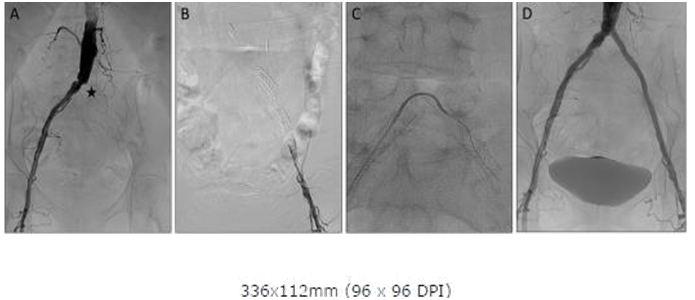

Abdominal angiography revealed a left PICTO with ostial left common Iliac occlusion (Figure 2A). Lt femoral access was obtained but despite multiple attempts the occlusion could not be crossed from below with an 0.035 wire (Figure 2B) and appeared to enter a dissection plane. A CC was again positioned in the aortic bifurcation and a 0.035 glidewire was then slowly advanced through the PICTO from the CC above and used to cross the PICTO. Once the wire crossed the occlusion with the support of the contra catheter and was confirmed to be in the true lumen, it was snared from below and externalized through the left sheath (Figure 2C). The procedure was then completed with standard stenting with final kissing balloon dilatation with an excellent angiographic outcome (Figure 2D) and the patient was complication free on follow up at one month.

Figure 2A: Abdominal Aortogram showing ostial Left Common Iliac occlusion (asterisk).

Figure 2B: Angiography from sheath inserted in Left femoral showing distal cap and wire in subintimal plane and Contra catheter in distal Aorta.

Figure 2C: After crossover with Contra and angled glide from right and snaring the wire from the left sheath.

Figure 2D: Final Abdominal Aortogram after stenting showing good angiographic result.